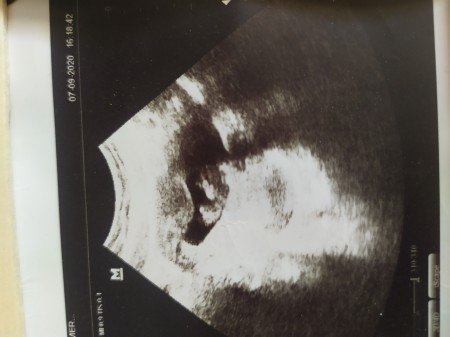

Sizce kız mı erkek mi

Belki şuan küçük ama tahmini olan var mı

9/5

Daha çok küçük neler olduğu belli değil bile tahmin edilmesi de çok güç ben 11 haftalık hamileyim ben bile öğrenip yada tahmin yapın diyemem buradakilere

O kadar küçük ki hiç brsey bllı dgl suan

Belli degil cnm...13haftalik hamileyim hele cinsiyyeyjni bilmiyom sadece foktor tahminini bkliyom.o kdr

Cook erken normlde 14 16 gibi öğrenirsin ama o bile bazen kessin net olamayabiliyir